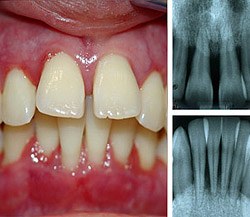

Пародонтит (от -греч. παρα- - около, ὀδούς - зуб, -ит - воспалительного характера), иначе воспалительное заболевание тканей пародонта, характеризующееся прогрессирующим разрушением нормальной структуры альвеолярного отростка челюсти. Пародонтит распространён достаточно широко, как и другие заболевания пародонта.

Заболевание проявляется прогрессирующей деструкцией альвеолярных отростков (а именно, зубных ячеек этих отростков). На течение пародонтита неблагоприятно влияет отложения зубного камня, неопрятное содержание полости рта. Симптоматика начальных стадий скудна - кровоточивость дёсен, слабость зубной связки, иногда - вязкая слюна, налёт на зубах. При активном течении вследствие быстрой деструкции альвеолярных отростков выпадают зубы.

Более разнообразны клинические проявления при обострении пародонтита: воспаление десны, гнойные выделения из зубо-десневых карманов, неприятный запах изо рта, патологическая подвижность зубов, их смещения. Нередки абсцессы и свищи на десне, увеличение и болезненность подчелюстных лимфатических узлов. Хроническое течение с частыми обострениями пародонтита могут сопровождаться микробной аллергией.